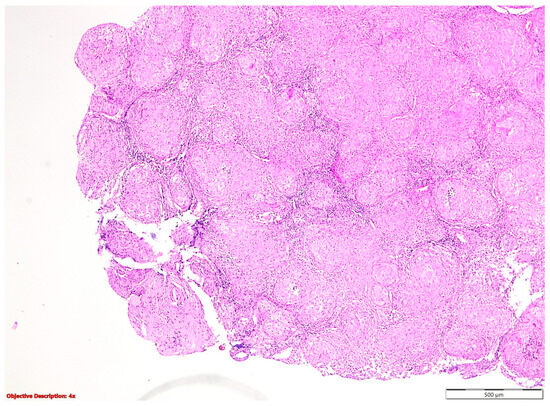

In the nine cases of NSCLC associated with granulomatous lesions, five of them were represented by active tuberculosis (Figure 2) and four by sarcoidosis (Figure 3).

Figure 2. Tuberculosis: (a) gross examination (fibronecrotic lesion—caseous necrosis); (b) microscopic examination (necrotizing granuloma including Langhans giant cells and epithelioid histiocytes; HE, 400×); and (c) microscopic examination (BAAR; Ziehl Neelsen, 1000×).